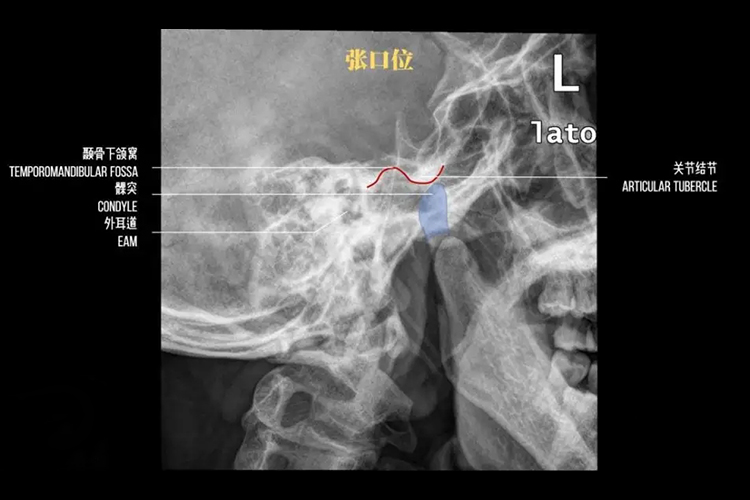

颞颌关节X线检查时需摄取两侧的侧位闭、张口位片,可显示出骨组织及含气空腔,常用于观察外伤骨折、颌面骨炎症、肿瘤性病变以及颞颌关节病变等,正常X线表现如下:

颞颌关节张口位:X线检查可见受检者的上下颌远离,为张口状态,下颌关节突(髁状突)前移至骨关节结节前下方,两侧颞颌关节活动度相等。